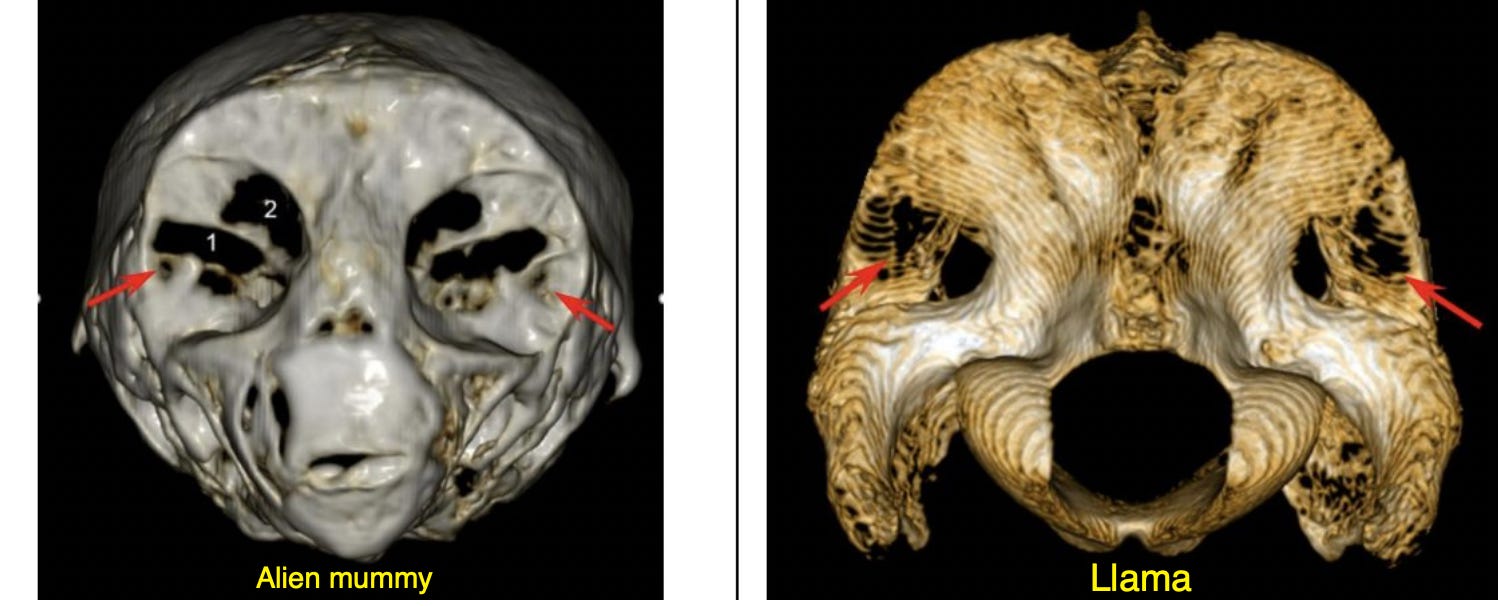

In 2021, the International Journal of Biology and Biomedicine published a study with three authors titled, “Applying CT-scanning for the identification of a skull of an unknown archaeological find in Peru.” They analyzed scans of the alien mummy skulls and concluded “the head of the small body is largely made of a deteriorated llama braincase.” Apparently, llama skulls develop face-like crinkles in the back when they decompose, so if you cut a llama skull in half and turn it around, do some careful carving to bring the features out better, Shazam, alien face.